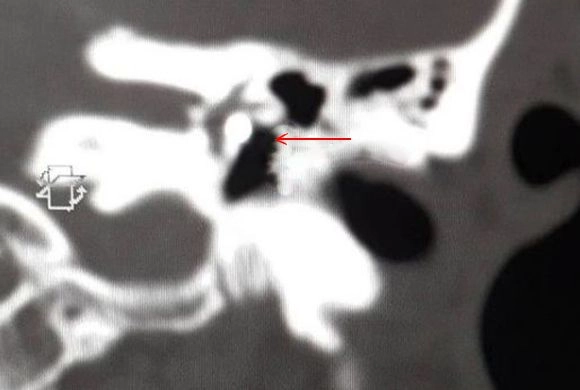

В Пензе врачи нашли за барабанной перепонкой сварщика осколок металла

Пациент поступил в больницу с подозрением на инсульт. В процессе обследования медики увидели, что за барабанной перепонкой есть инородные тела. На снимке просматривались окалины, которые попали в ухо при сварочных работах.

— Эндоскопическая операция по извлечению металлических осколков длилась 45 минут, — сообщили в клинической больнице №6, уточнив, что операция проводилась под руководством завотделением, главного внештатного отоларинголога Андрея Федина.

Попадание окалин в ухо — не редкость для сварщиков, в первую очередь это говорит о несоблюдении техники безопасности . Обычно осколки остаются в слуховом проходе и повреждают барабанную перепонку, но не оказываются за ней.